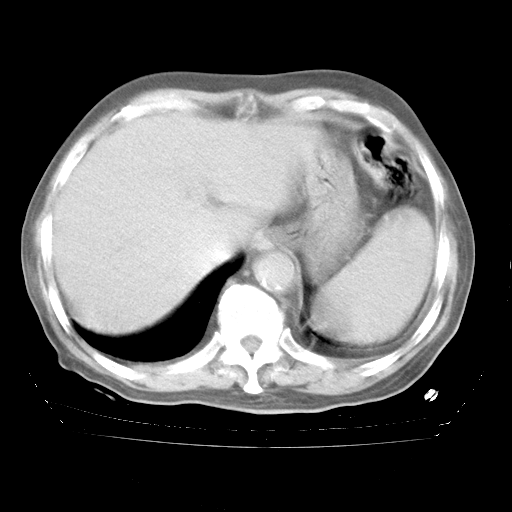

今天部分检查

轻微咳嗽,无痰,(体温正常时)R20次/分,P75次/分,双肺底、腋下可闻及少量捻发音。下肢轻度浮肿。

腹部B超:胆囊壁增厚,肝、胆、胰、脾、肾无异常,肠系膜淋巴结、腹膜后淋巴结无增大。

增加治疗:异烟肼、利福平、乙胺丁醇,静滴左氧氟沙星、参麦注射液。甲强龙从80mg暂减为40mg。

强的松3月1日改为10mg qd,4月1日改为10mg qod。3月份以前的减量过程和环磷酰胺疗程需等明天查看记录(我岳父自己做的记录在他家里)。